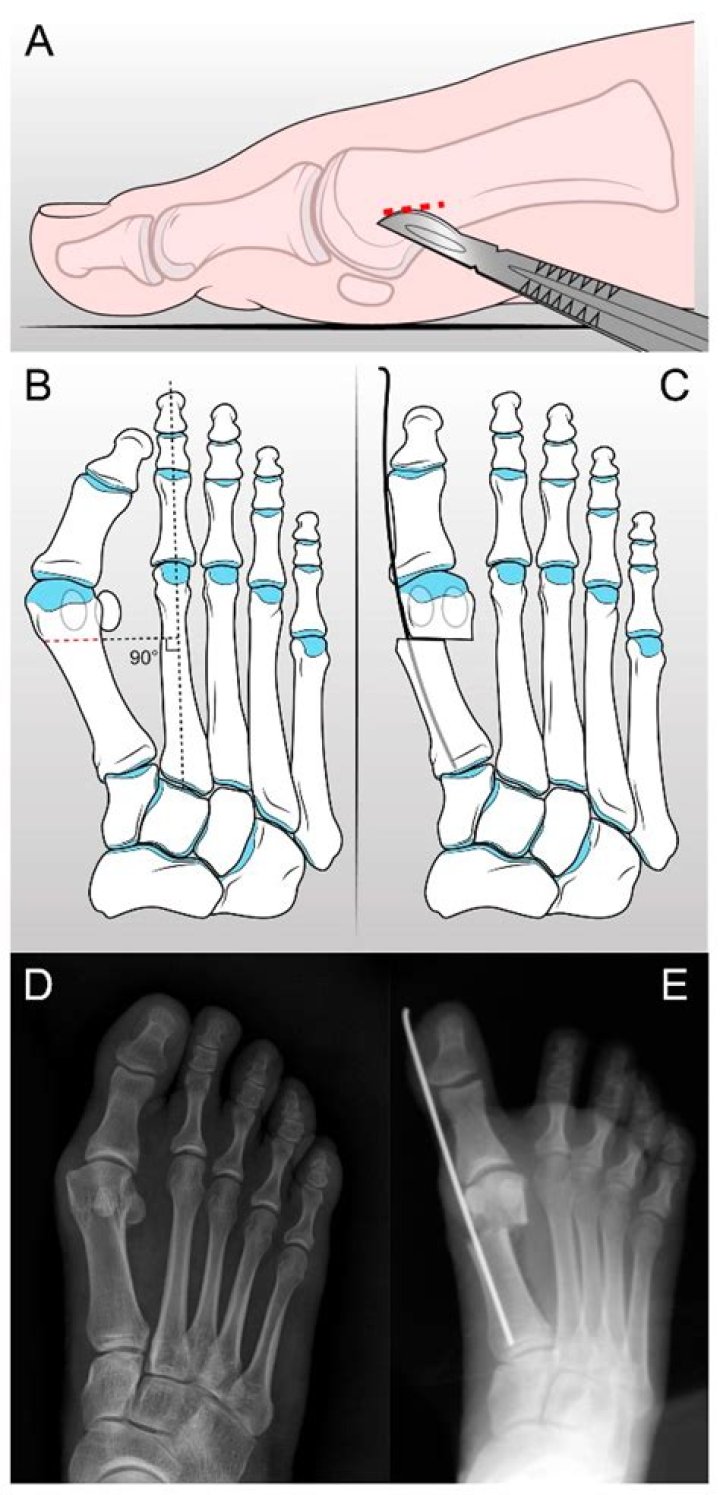

Surgical realignment of a bunion, also known as osteotomy, is an orthopedic procedure used to realign the toe joint in patients who have severe bunions. During surgery, your big toe and foot bones are straightened, and the joint that creates the bunion is positioned in position under the big toe.

A metatarsal osteotomy is a surgical procedure performed to treat a foot deformity. This surgery involves cutting the metatarsal bone of the big toe and realigning the bone to correct the deformity.

What is osteotomy surgery?

Modified McBride’s bunionectomy is a useful procedure for the correction of hallux valgus (bunion). Although it was originally described as an isolated technique, it is much more commonly performed in conjunction with proximal metatarsal osteotomy or tarsometatarsal arthrodesis in contemporary practice.